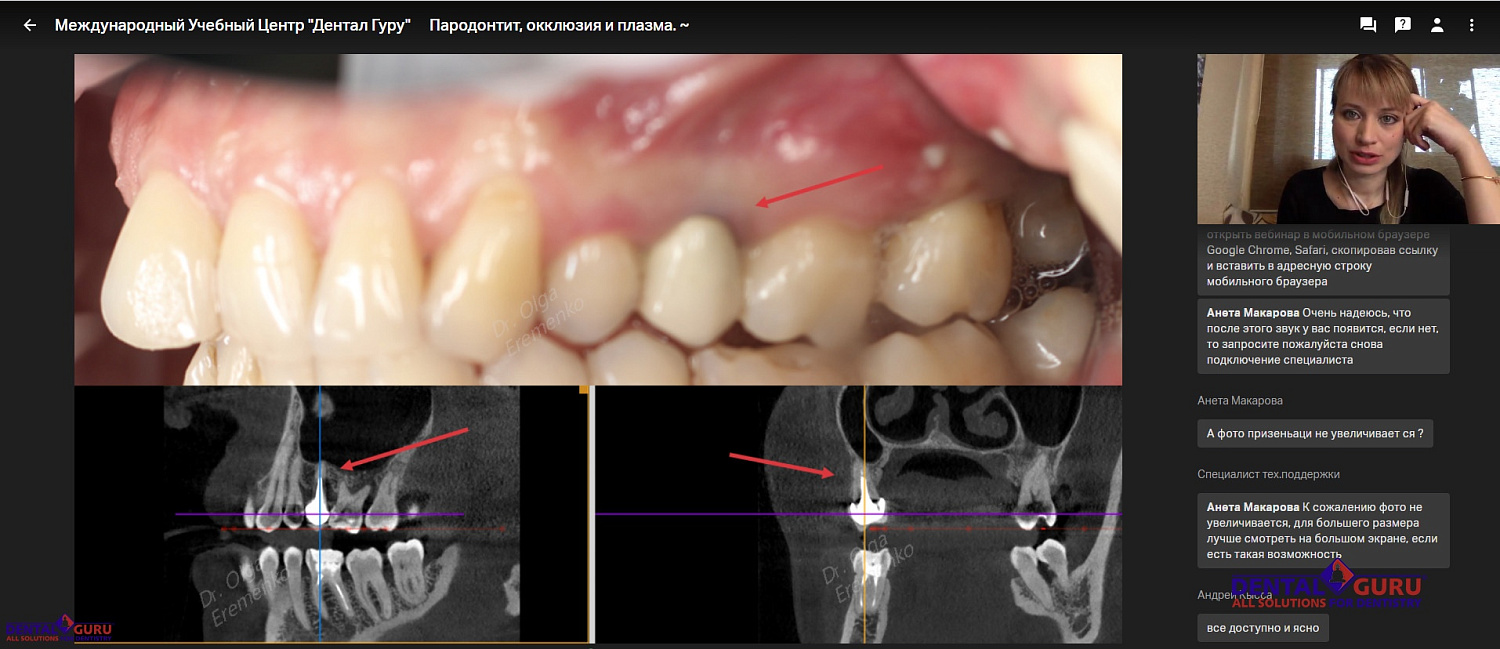

Взаимосвязь пародонтита и окклюзии настолько важна, что лектор Учебного Центра Дентал Гуру Ольга Сергеевна Еременко не рекомендует приступать к лечению заболеваний пародонта без тщательной предварительной диагностики, в первую очередь, КЛКТ-исследования. Какие еще методы определения причин заболеваний пародонта существуют, узнали участники онлайн-курса Пародонтит, окклюзия и плазма 29 мая.